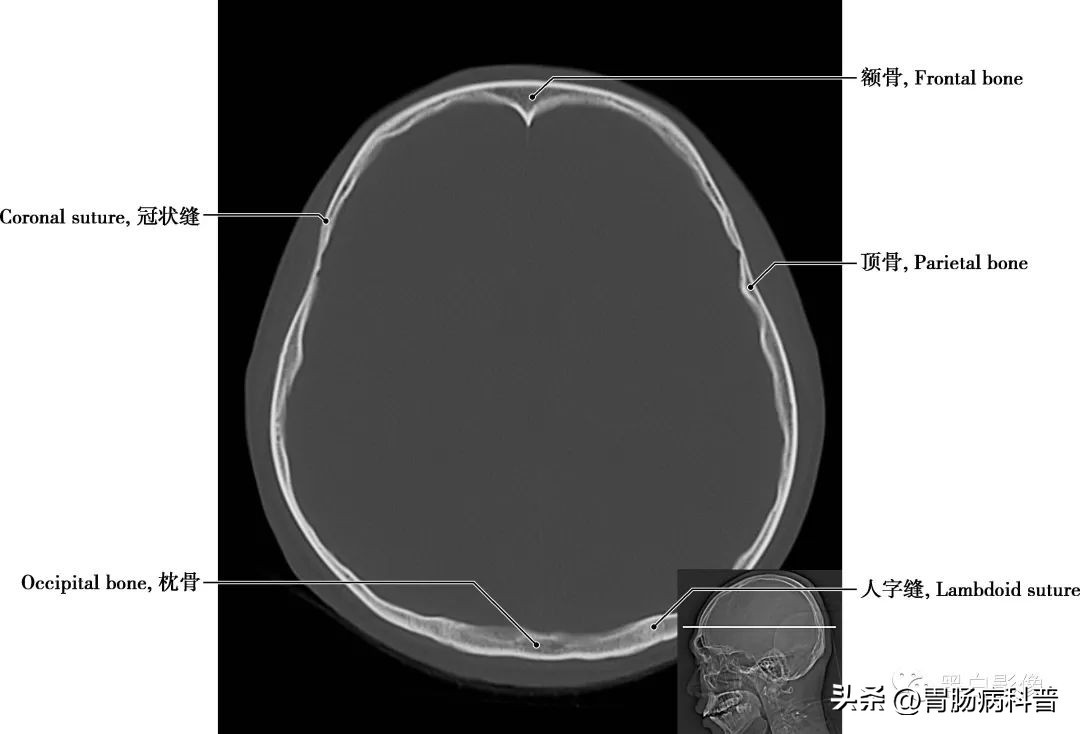

图1-2-3 经中央旁小叶上部轴位切面

额骨 位于前额处,分为三部分,即额鳞,大而垂直,在前额;眶部,环状或水平,对眼眶顶部和鼻腔的形成至关重要;鼻部,与鼻骨和颌骨的额突在鼻根部形成关节,其前与筛骨和鼻骨相连,后通过冠状缝与顶骨相连